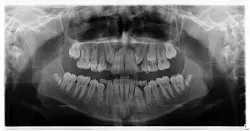

My hygienist had taken radiographs prior to me coming in.

Diagnosis: Mesiodens tooth

- Diagnosis is primarily via radiograph and can be confirmed by taking multiple angles using intraoral and extraoral radiographs (i.e., panoramic, periapicals, etc.). Furthermore, three-dimensional CBCT scans allow dialing in on the palatal location of the mesiodentes and their relationship to adjacent teeth. Delayed or altered eruptions of adult dentition also give rise to the suspicion of mesiodentes. Other common signs include cyst formation and crowding.

- Treatment of mesiodens varies. Although typically asymptomatic, they are “often extracted for aesthetic reasons, to allow the eruption of other teeth, orthodontic reasons, and/or suspected pathology.”3